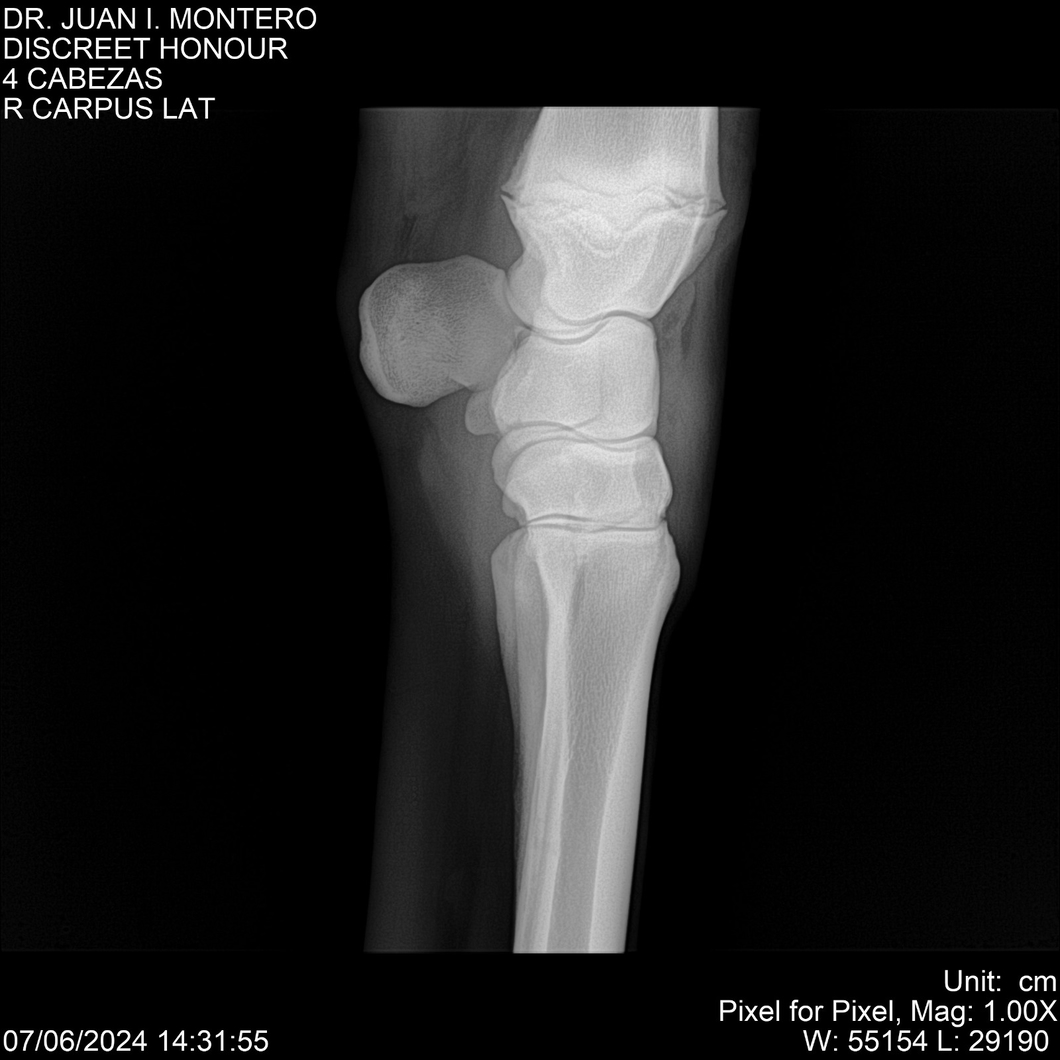

LOTE 6, DISCREET HONOUR 🔥 🔥 🔥 Lote Anterior Volver al remate Lote Siguiente Ficha Contacto Montevideo - Ficha del Lote Identificador: #281093 Categoría: Yeguarizos Montevideo - 82 Visualizaciones ClicData Contacto Empresa: Abelenda N. R., Walter Hugo Nombre*: Teléfono* : E-mail* : Mensaje Enviar Registrese gratis Este contenido Exclusivo está disponible sólo para usuarios registrados Ingresar